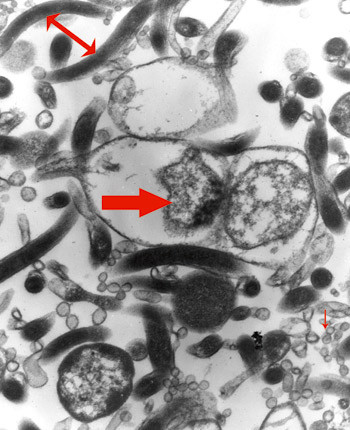

B. burgdorferi sensu lato inndeles i minst 13 ulike genospesies. Lyme-borreliose forårsakes vanligvis av de fire genospesies av B. burgdorferi sensu lato: B. afzelii, B. garinii, B. burgdorferi sensu stricto og nylig funnet B. spielmanii (3, 4). Bakterien er en gramnegativ bevegelig spiroket (fig 1) som måler 0,18–0,3 x 15–30 µm, er spiralsnodd og har 7–11 periplasmatiske flageller. Bevegelighetsrelaterte gener opptar over 6 % av genomet til bakterien. De unike flagellene gjør at den kan bevege seg i viskøs væske og raskt disseminere (5). Bakterien kan være mikroaerofil eller anaerob, avhengig av genospesies og type. Den er også fakultativ intracellulær (6–9).